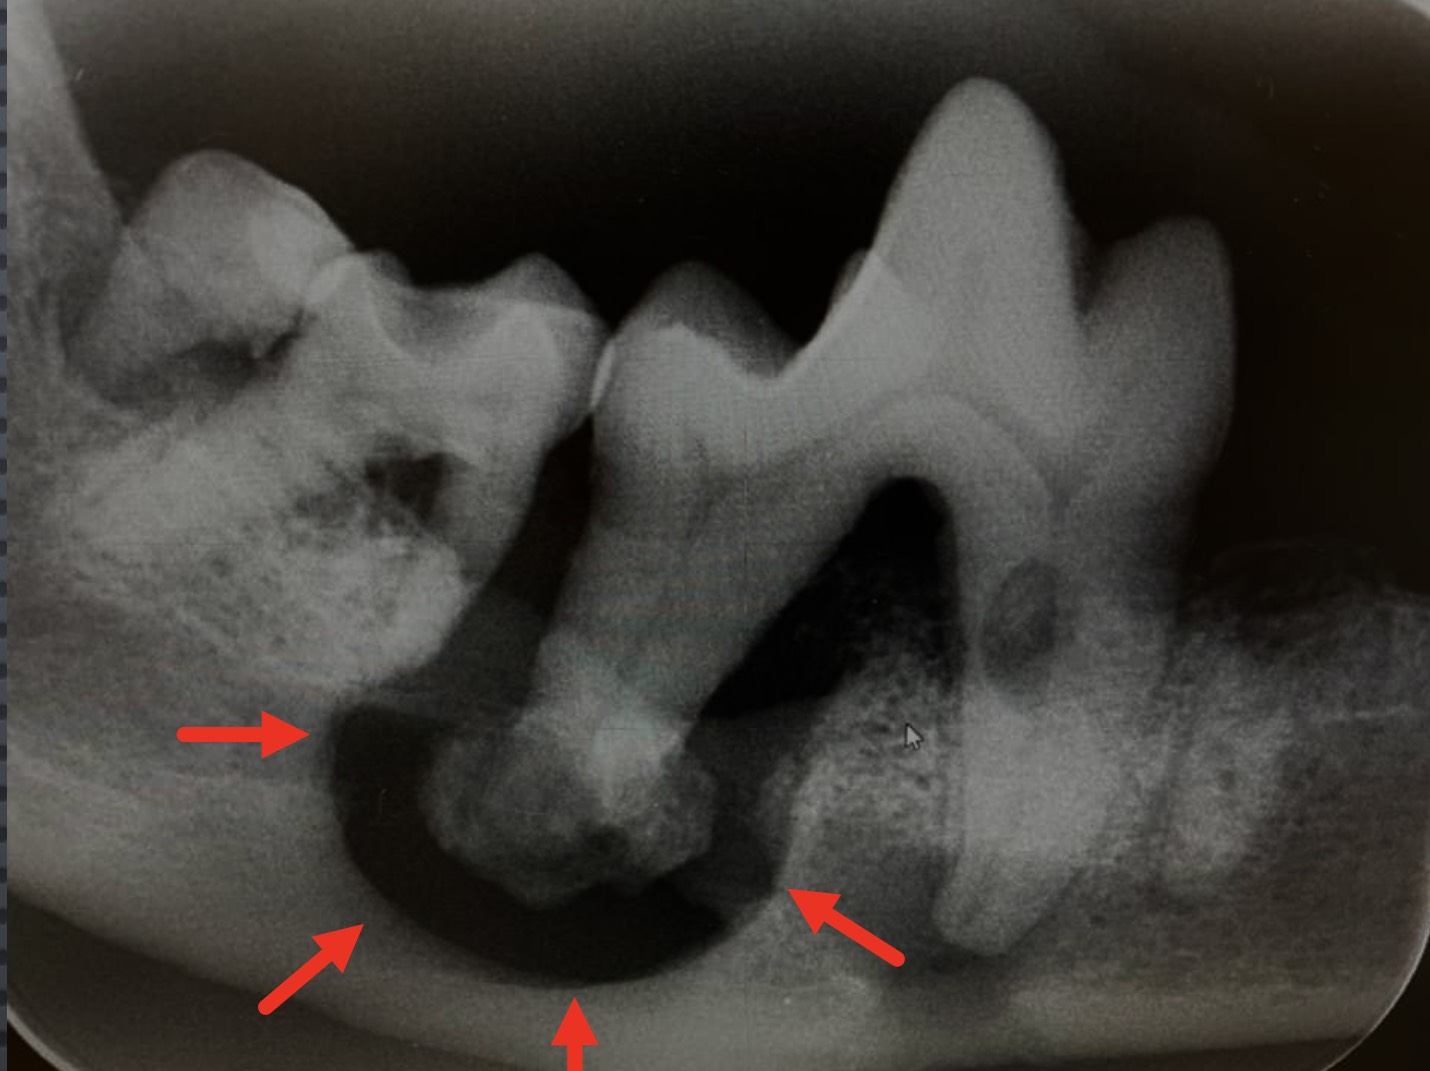

炎症反応によって歯ぐきや歯根周囲の骨が破壊されたり、(いわゆる)歯槽膿漏になったりします。

さらには、骨が溶けることによってアゴの骨が折れることもあります。

※歯周病により歯根周りの骨がとけています。